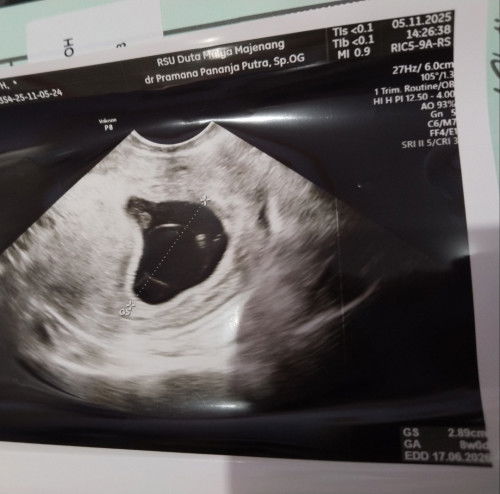

Kehamilan 9w

Ada yang sama engga ya bun 3mgg lalu usg udah ada bakal janin, hari ini usg tp kok belum ada janin ya? Disarankan 2mgg usg ulang #mohonbantujawabbunda #Sharingdong_Bund

semoga yg ditakutkan tidak terjadi ya bun. kudoakan segera ada kabar baik minggu depan sdh ada janinnya dan djj. soalnya klo smpe 12w terlewat dan blum ada janin, kemungkinan hamil BO. tpi semoga ngga yg penting asam folatnya tetap dikonsumsi setiap hari, supaya membantu pembentukan janin. tetap berpikir positif ya bun

iya bun itu juga yang saya takutkan